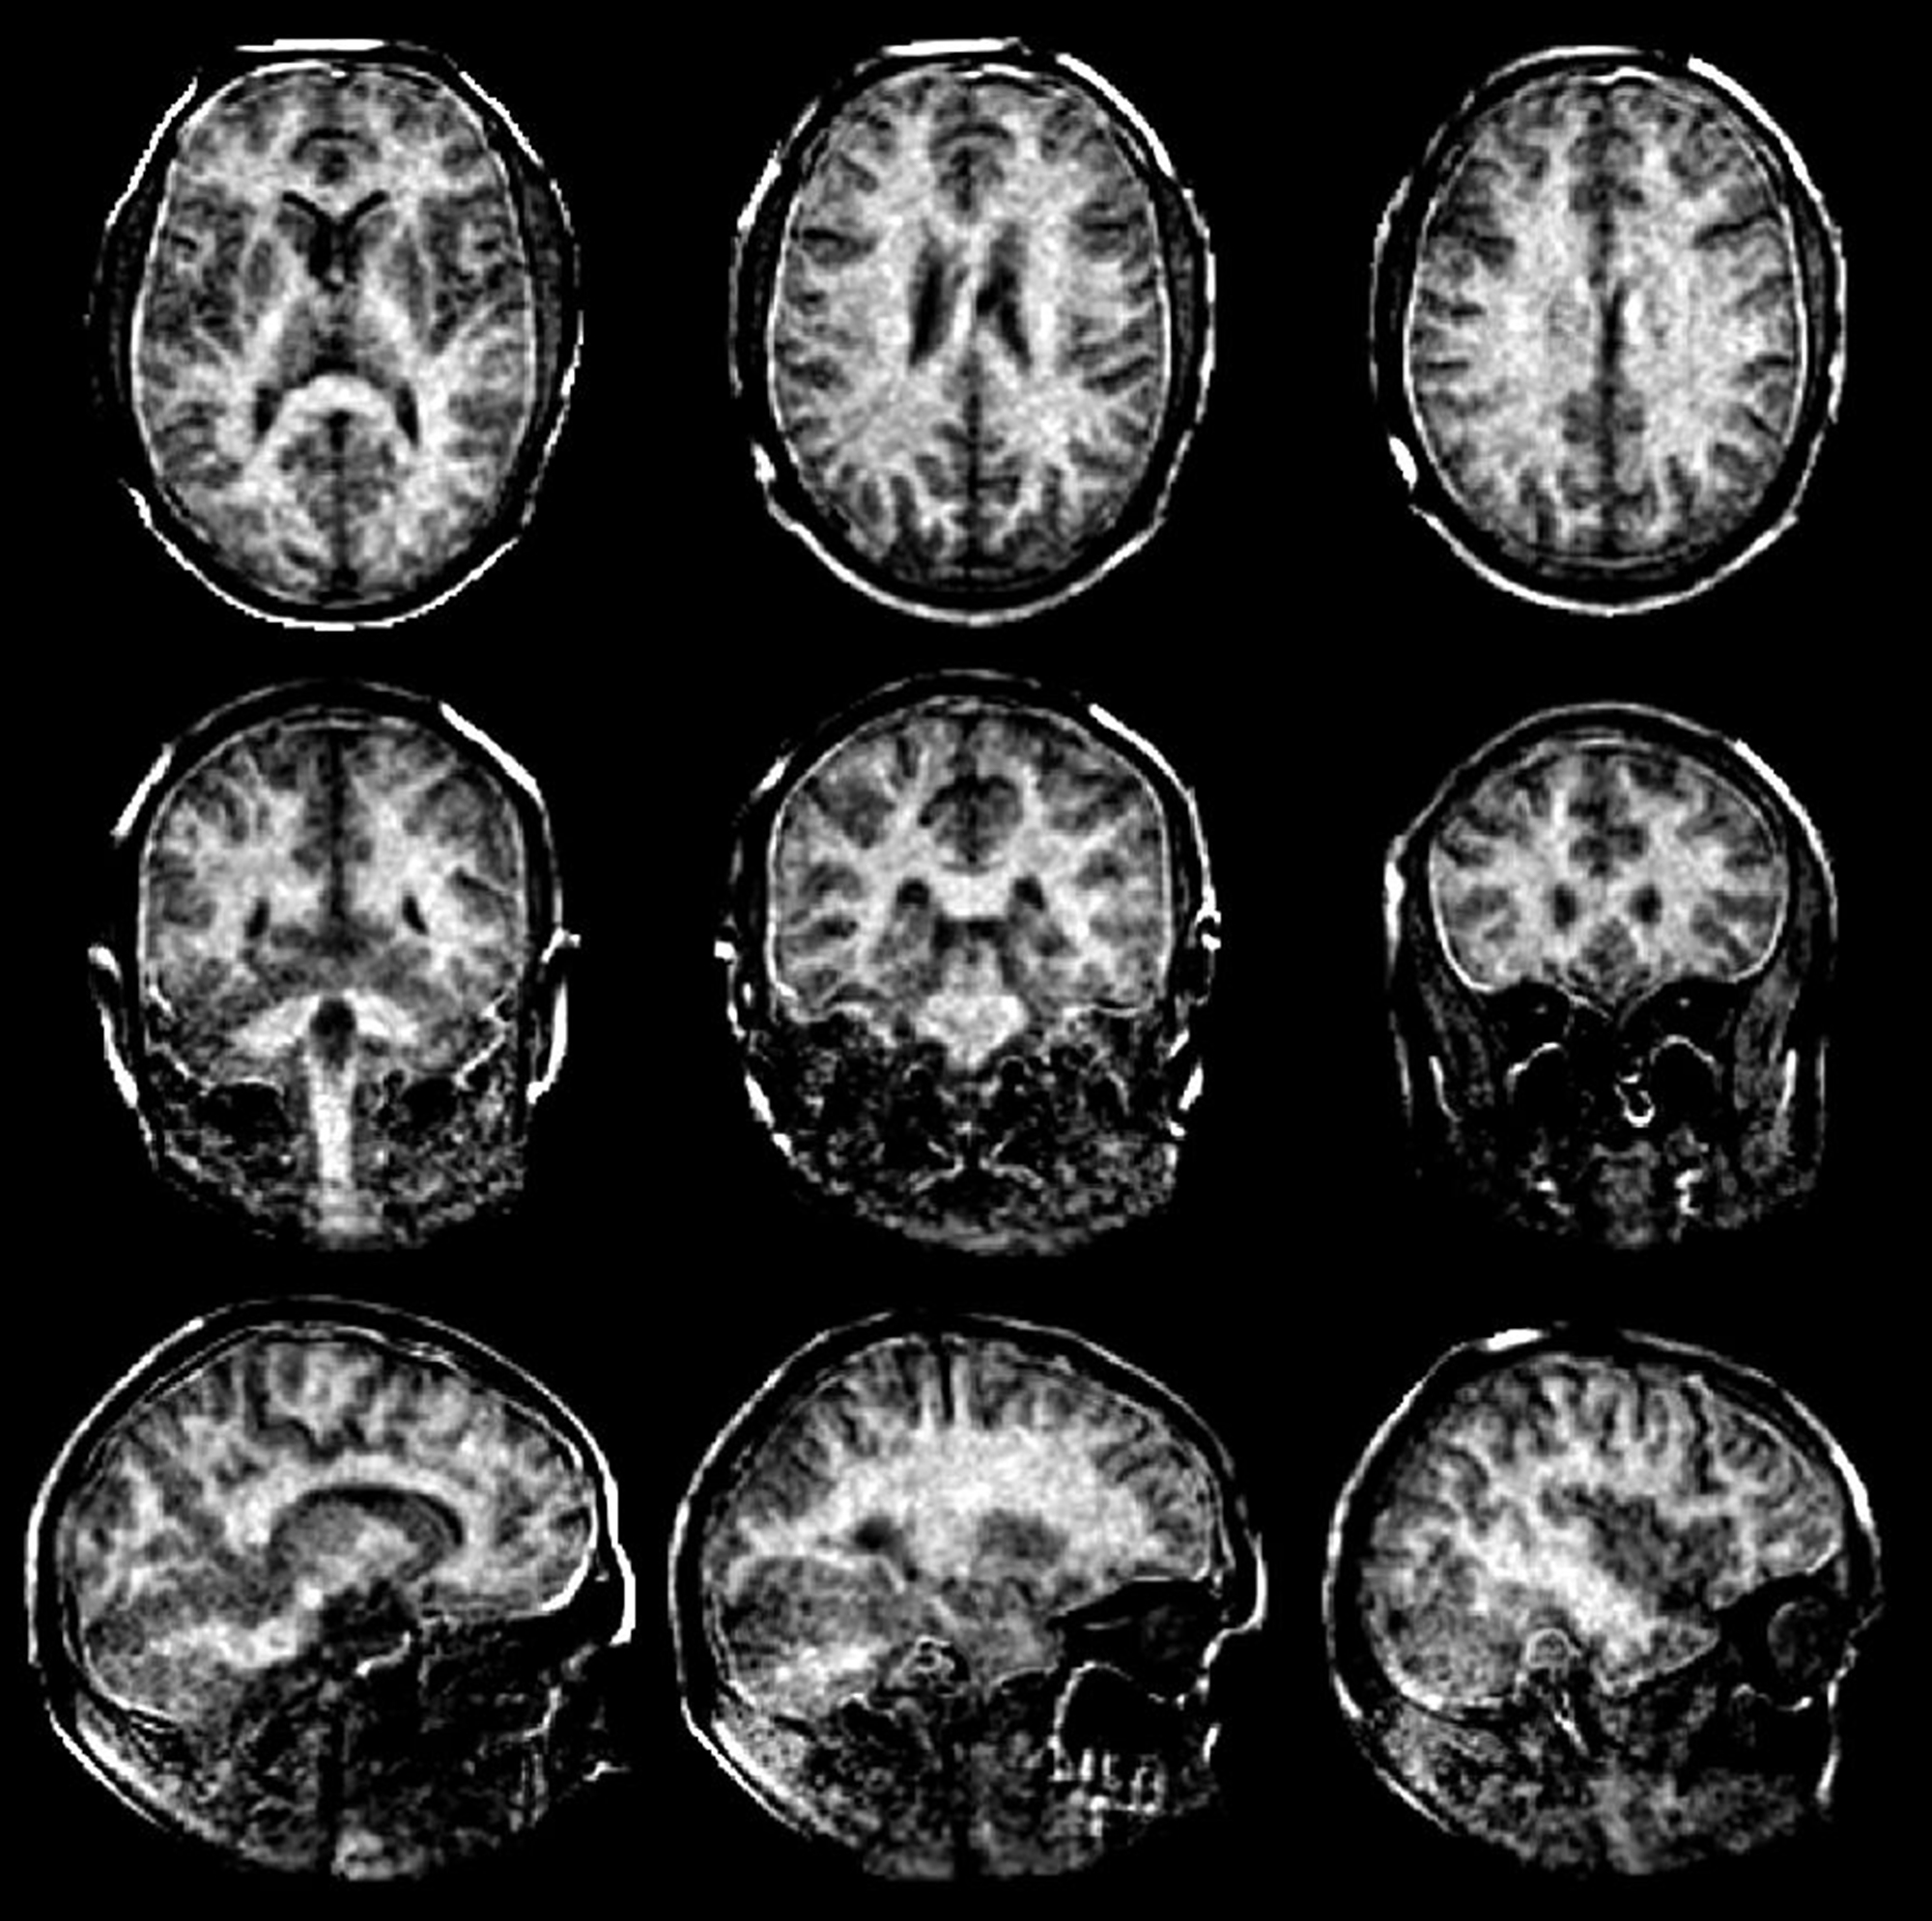

Das neue MRT-Verfahren der ETH-Forschenden löst dieses Problem und misst den Myelingehalt direkt. Es versieht die MRT-Aufnahmen des Gehirns mit Zahlenwerten. Diese zeigen, wie viel Myelin an einer bestimmten Stelle im Vergleich zu anderen Bereichen des Bildes vorhanden ist. So bedeutet die Zahl 8, dass der Myelingehalt an dieser Stelle nur 8 Prozent von einem Maximalwert von 100 beträgt, was auf eine deutliche Ausdünnung der Myelinscheiden hinweist. Grundsätzlich gilt: Je dunkler der Bereich und je kleiner die Zahl im Bild, desto stärker sind die Myelinscheiden reduziert. Mit diesen Angaben könnten Ärztinnen und Ärzte den Schweregrad und Verlauf von MS besser einschätzen.